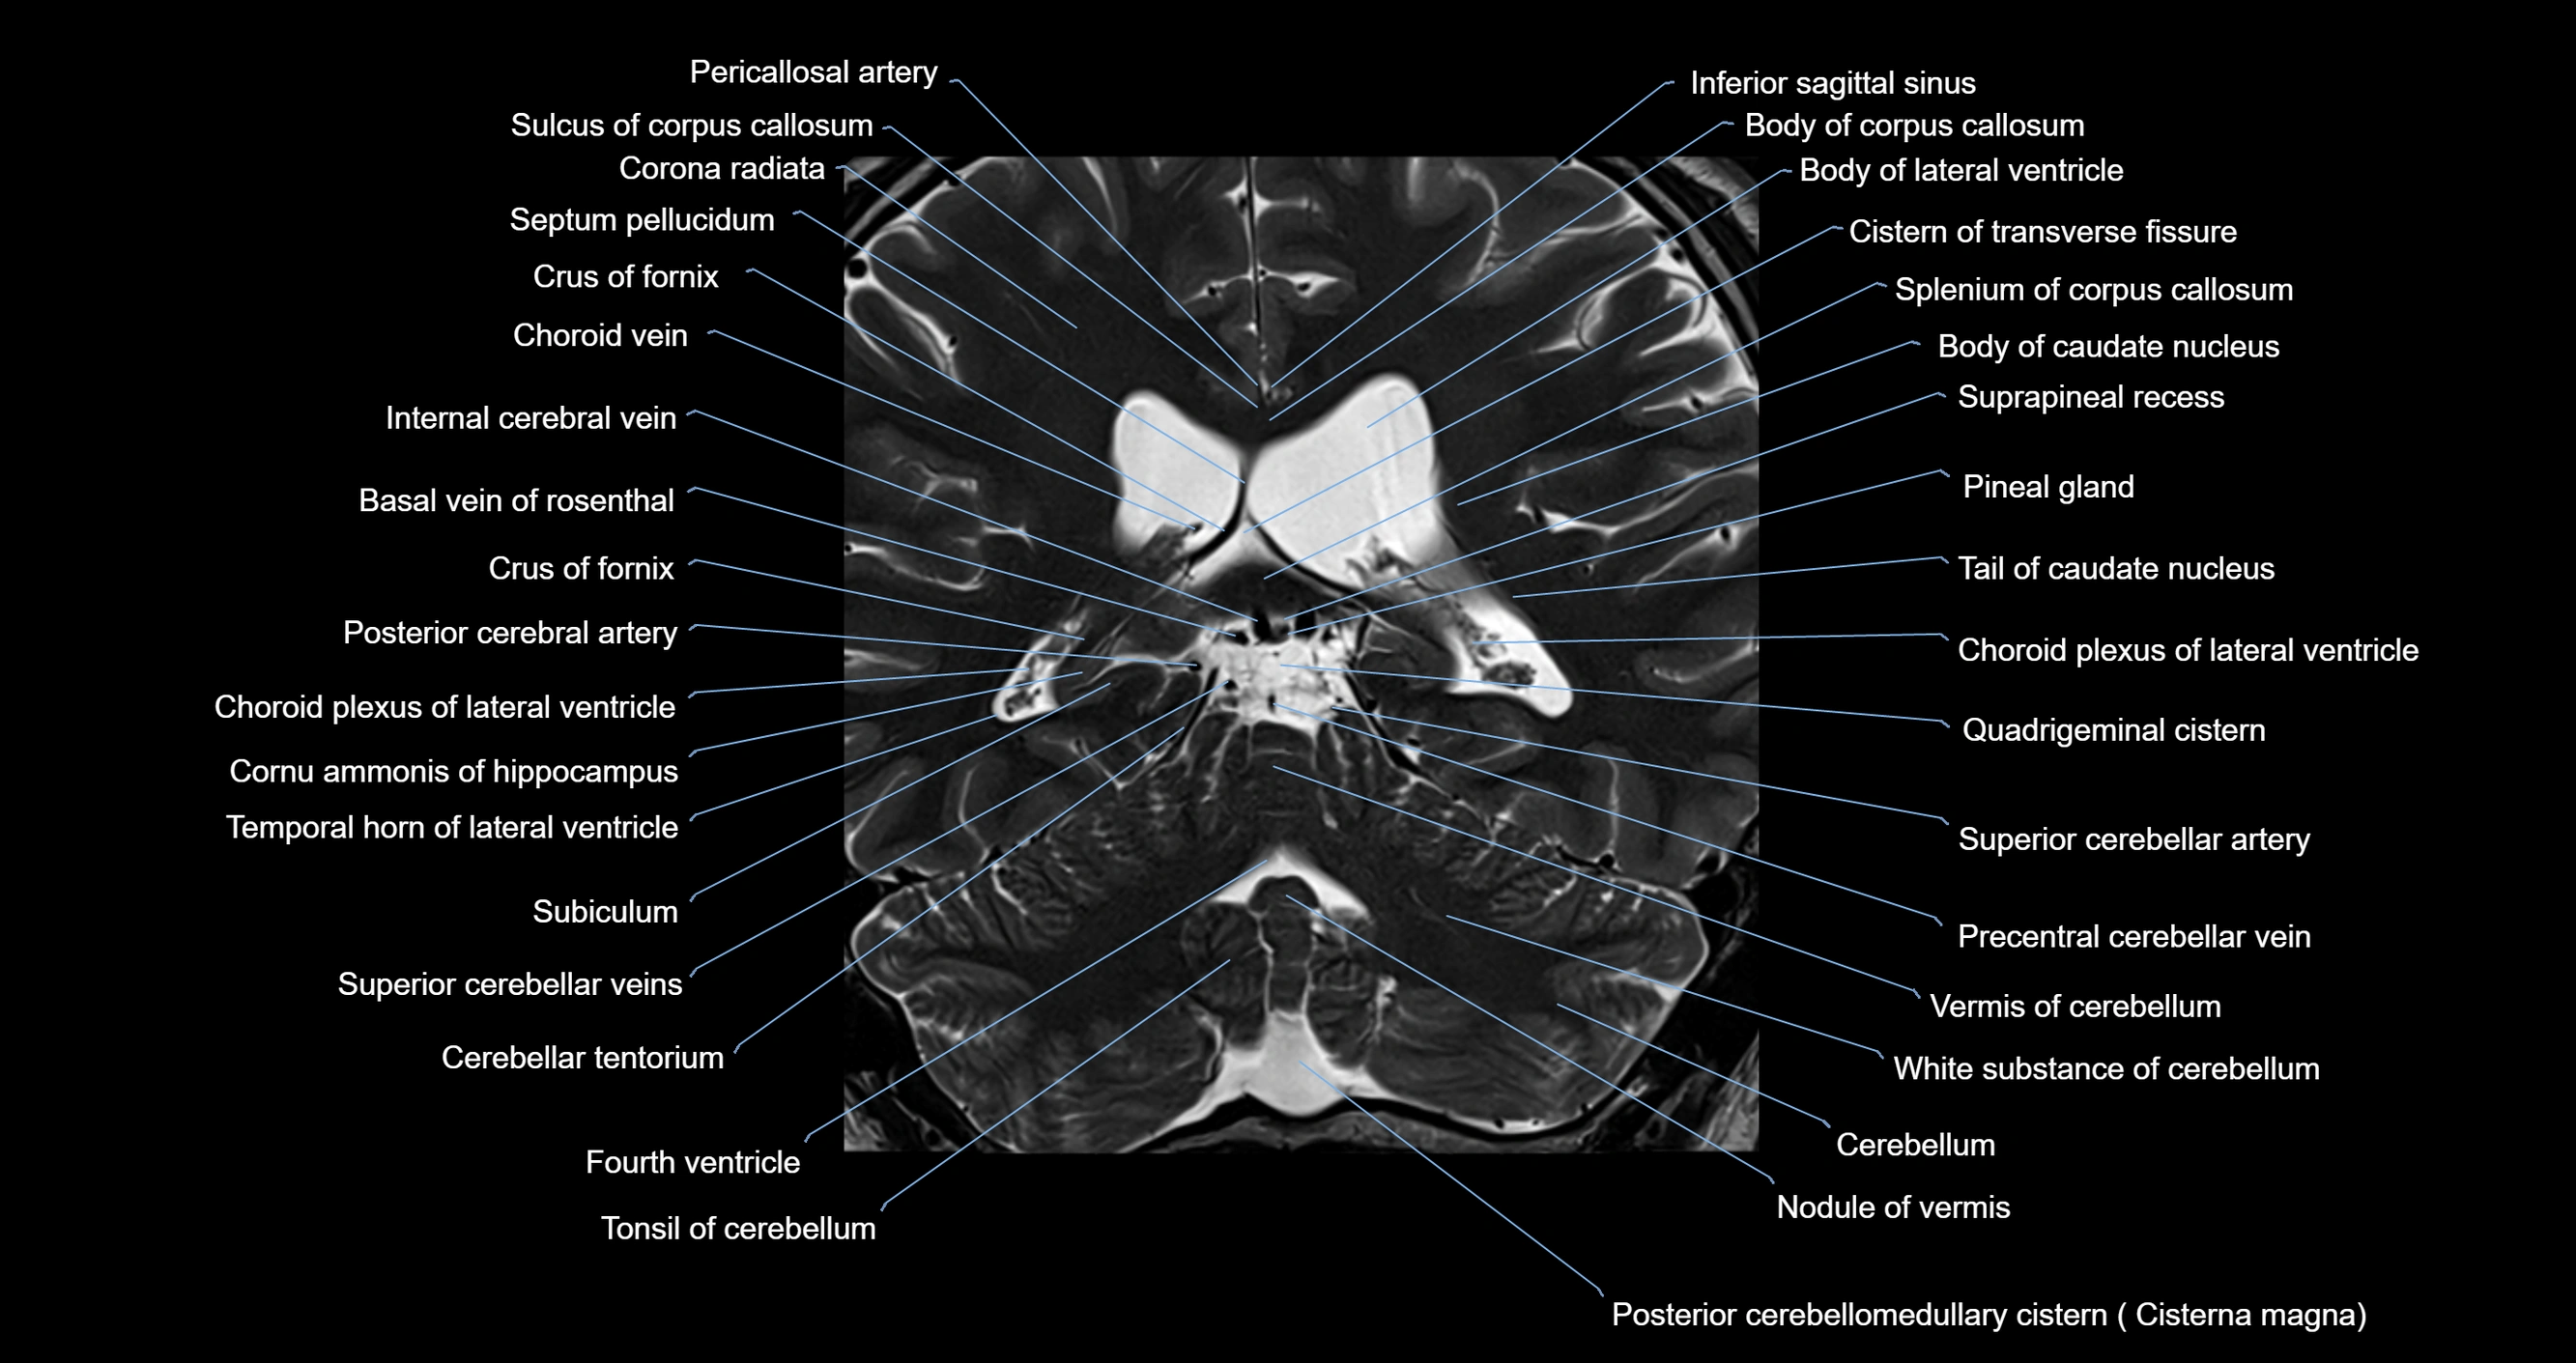

MRI images